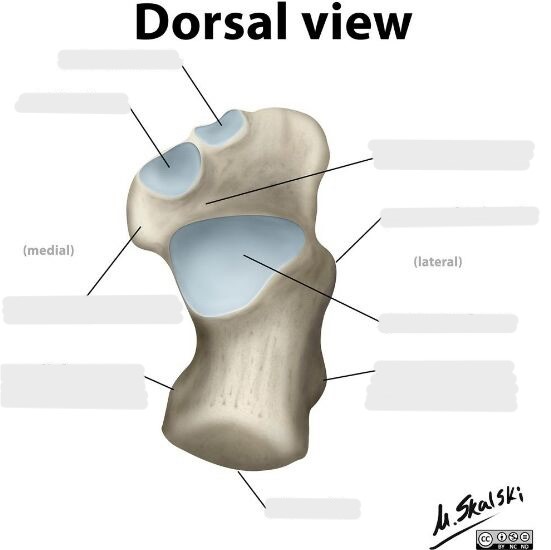

Label the 3 surfaces of the talus that articulate with the calcaneus